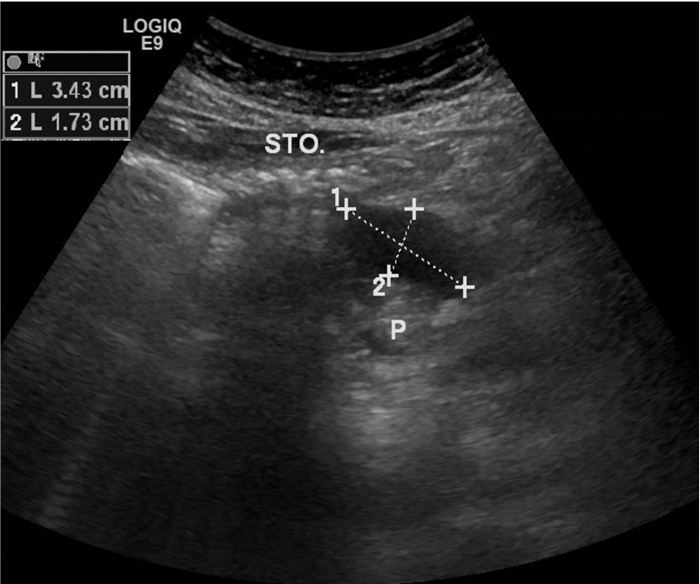

31例MSAP及SAP患者超声显示胰腺均肿大,边缘不规则,边界不清,胰腺实质回声分布不均匀,可见粗大强回声斑或低回声及无回声混杂,其中6例超声提示胰腺脓肿或胰周假性囊肿形成,呈类圆形低回声或无回声区,边界欠清(图 3);29例小网膜囊增厚,呈片状或块状增强回声带,部分内合并有无回声区(图 4)。

| 胰周假性囊肿形成,呈无回声区,内透声可,范围约3.4 cm×1.7 cm, 经手术证实; STO:胃;P:胰腺 图 3 重症急性胰腺炎(SAP)超声所见 |